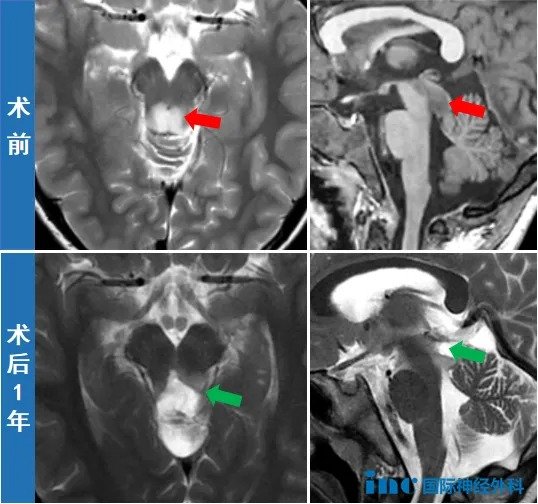

过去的一年,晓飞一家的心情宛如坐了一趟惊险的过山车——一开始只以为儿子得了一场小感冒,没想到感冒虽然好转,但影像上却显示出中脑背侧存在异常信号,疑似胶质瘤!金女士一家顿时陷入绝望,而且由于脑干位置特殊,儿子的手术风险太高,医生均建议保守观察。

“手术十分成功。”最终,好消息传来,金女士一家知道,她们正在脱离谷底,积极向上。术后2天,晓飞的各项功能均恢复,没有任何神经损伤,中脑顶盖的肿瘤也被成功切除,孩子已经可以下床走路。“孩子非常好,比我预想中的还要好!”巴教授连声称赞。

术后1年,巴教授表示:“看到男孩目前极佳的临床状况,真的令人欣喜。总而言之,这是一个非常令人满意的进展,我很高兴看到这名男孩处于如此好的情况。”